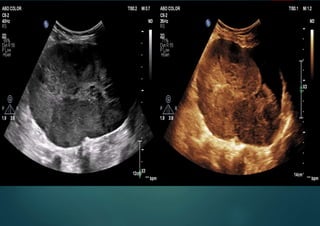

Stage 4 ovarian carcinoma with

ascites

Tumor with at least moderate blood flow, ascites, postmenopausal